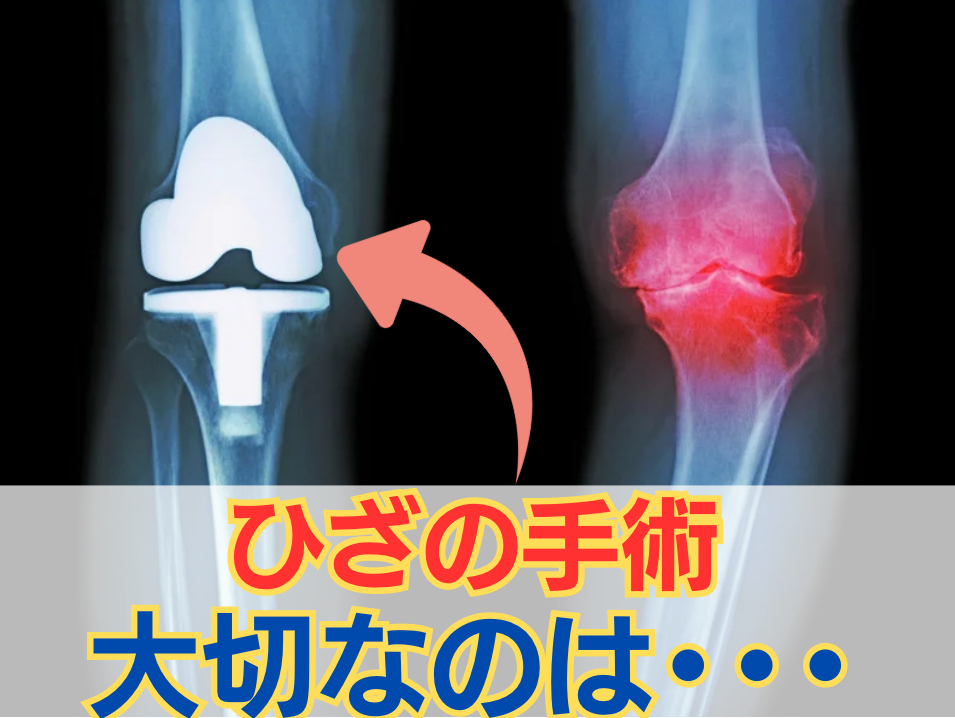

ひざの手術をしても元には戻りません

実は、ひざの手術をしても

完璧に曲げ伸ばしの範囲が

元通りになることは少ないんです。

人工関節置換術を受けても、

もともと可動域が狭い方は完璧に戻らず

制限が残ることがよくあります。